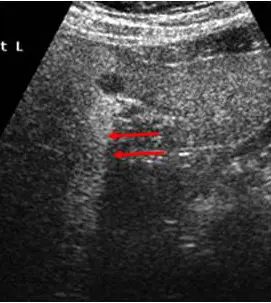

附圖為腹部超音波影像,箭號所指為何?

- 影像為一張灰階(B-mode)腹部超音波影像。

- 影像中上部可見一個邊界清楚的**無回音(anechoic,呈現黑色)**囊狀結構,通常代表內部充滿液體(例如:水泡 cyst 或血管)。

- 影像中紅色箭號所指的區域,位於該無回音結構的正後方(深處)。

- 觀察箭號所指區域,其回音強度明顯高於同一深度的兩側相鄰組織,呈現一道**高回音(hyperechoic,呈現較亮偏白)**的柱狀帶。

- (A) 遠方回音增強(distal enhancement / posterior acoustic enhancement):正確。當超音波穿過衰減係數極低(通常是充滿液體,如囊腫、膽囊或膀胱)的結構時,超音波能量被吸收和散射的程度極少。由於超音波儀器的時間增益補償(Time Gain Compensation, TGC)是假設超音波在所有組織中的衰減率為均勻的,這會導致穿越低衰減結構後的超音波反射訊號被相對「過度放大」,使得該結構後方